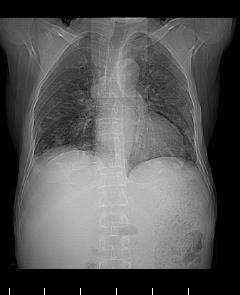

两肺示有散在大小不等类园形边缘不整密增高影.

考虑多发性转移瘤.请各位老师指导.

两肺及胸膜多发性转移瘤。

多发肺转移瘤及胸膜转移。

双侧胸壁见多发结节软组织密度灶,两肺内见广泛结节状、面团样影,两肺及胸膜多发性转移瘤。支持